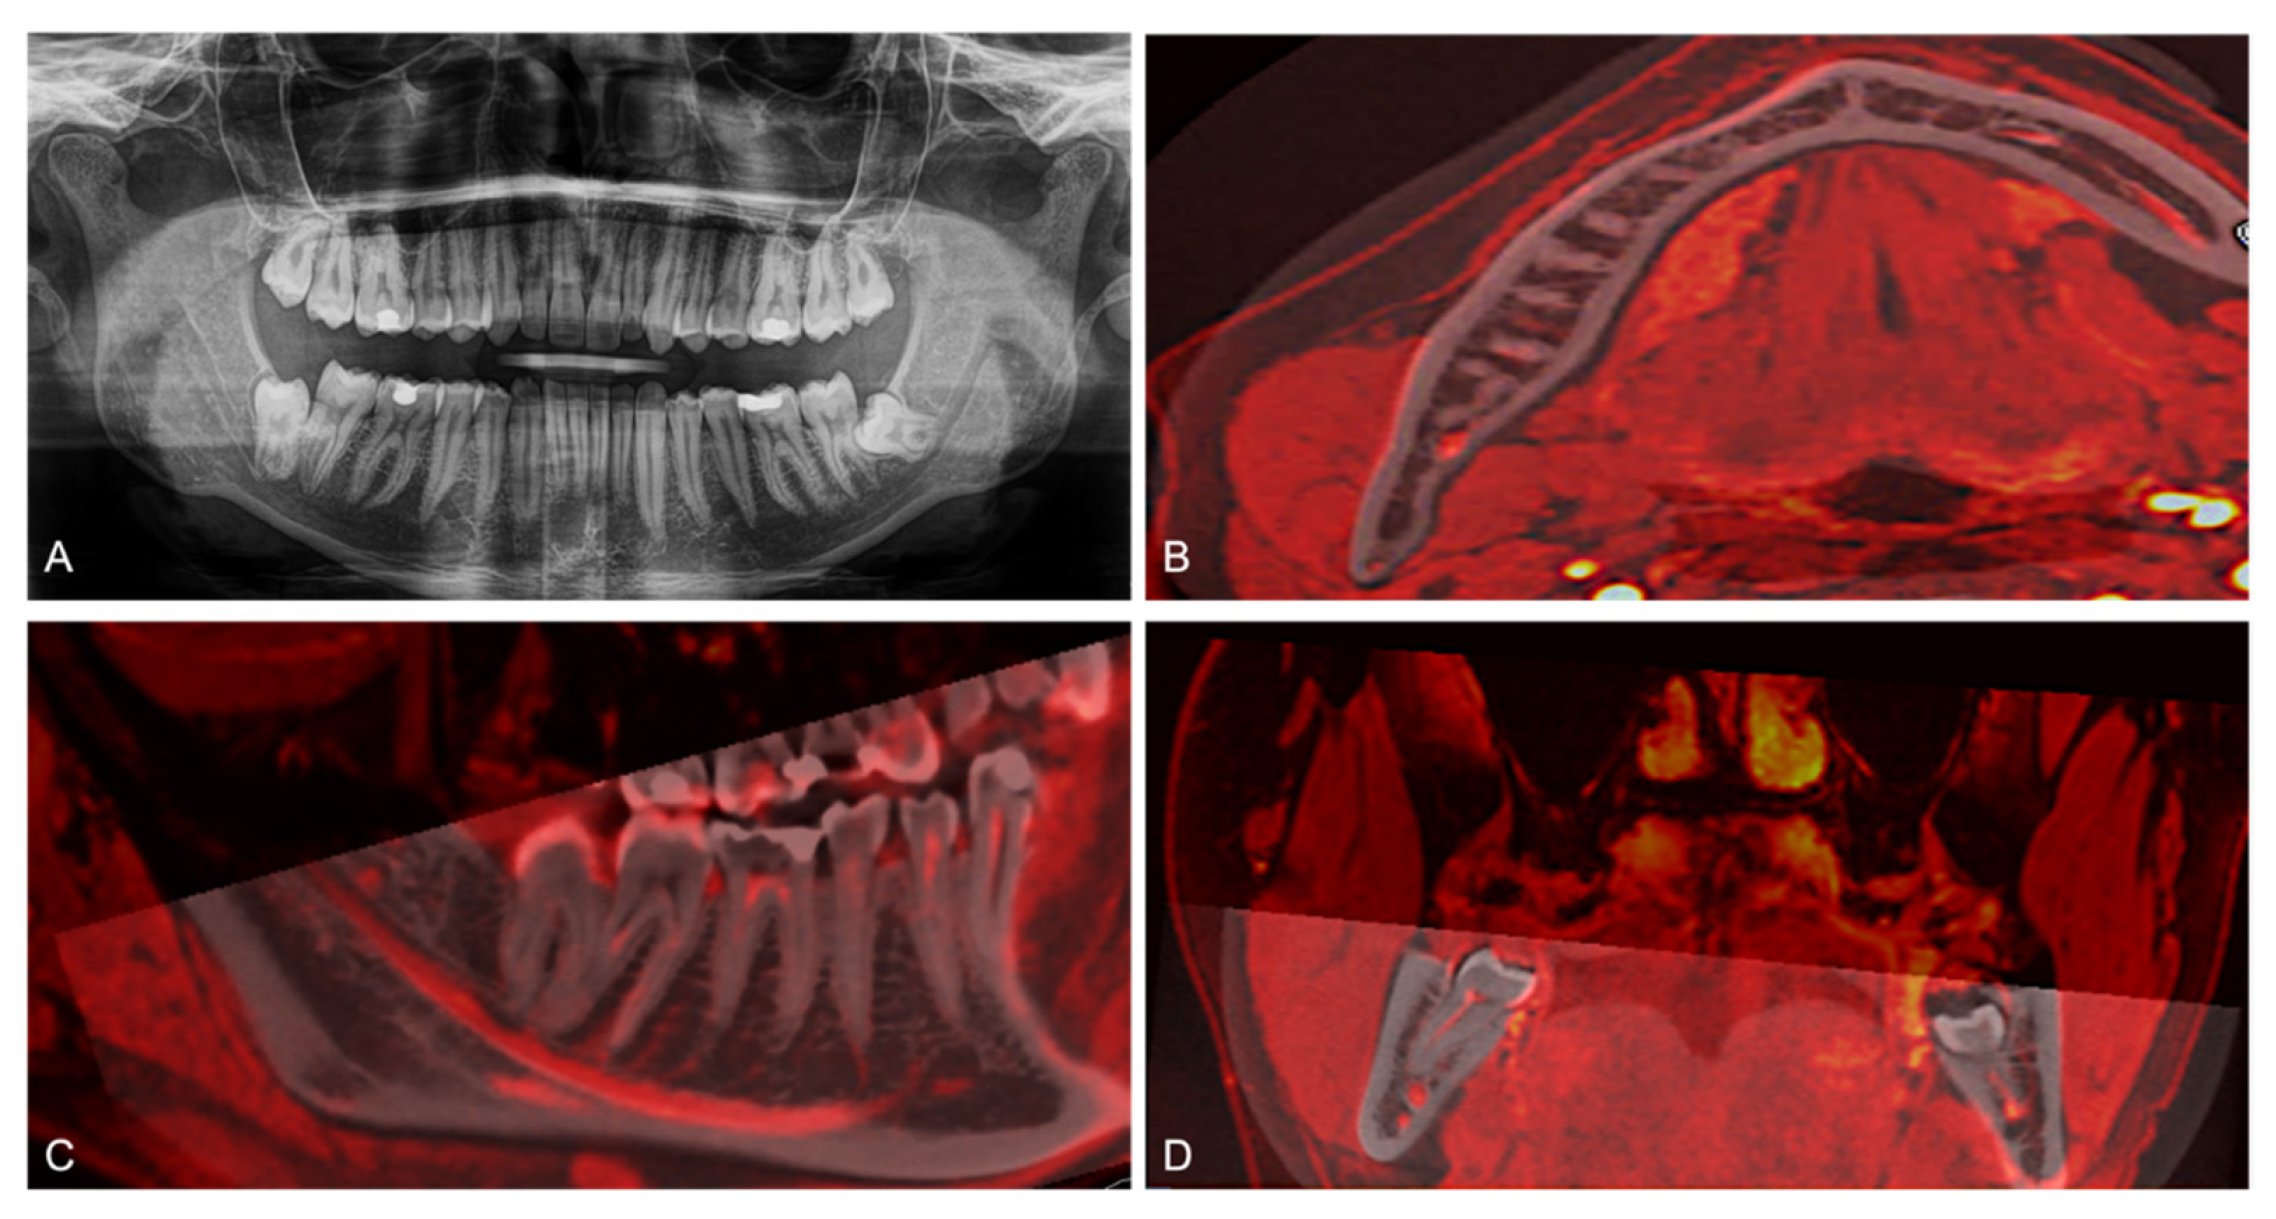

Figure 4. (A) Two-dimensional panoramic radiography (PAN) of a study participant, CBCT and MRI scans of a study participant were transferred to OnDemand3D and fused using the “automatic registration” function at an equal slice thickness of 0.5 mm. The MRI scan was labeled red, and conventional grayscale values displayed the CBCT scan. Axial (B), sagittal (C), and coronal (D) fused CBCT/MRI images are visualized.

CBCT and MRI scans of each study participant were transferred to OnDemand3D and fused using the “automatic registration” function at an equal slice thickness of 0.5 mm. The MRI scan was labeled red, and conventional grayscale values displayed the CBCT scan. If the fusion was rated as not perfect, in all cases, these images were manually re-registered in consensus using trial and error until a complete overlapping in the coronal, axial, and sagittal planes was achieved. The final CBCT/3D-DESS MRI volumetric fusions were used for evaluation by defining the retromolar and molar region as regions of interest (Figure 4).